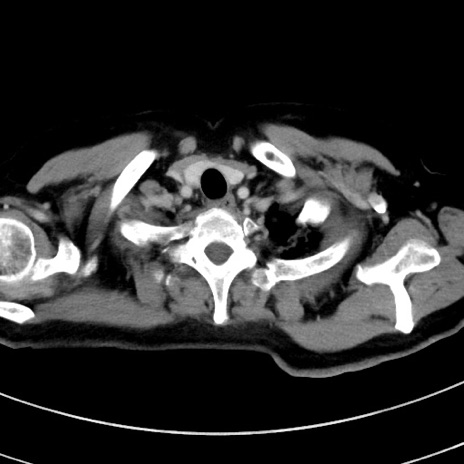

症例9(横断像)

【症例】 60歳代女性

【主訴】むかつき、みぞおちの痛み

【現病歴】3日前よりむかつきがあり、食事がとれない。

【既往歴】糖尿病

【身体所見】発熱なし、心窩部圧痛軽度あるも、腹膜刺激症状なし。

【データ】WBC 7400、CRP 1.92